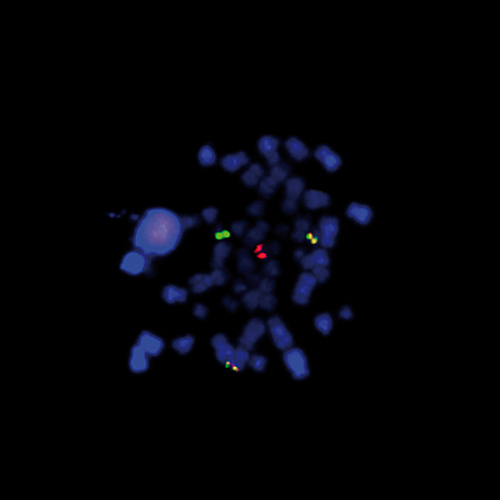

RNA Positive Control Probe is intended for use as a positive control in formalin-fixed, paraffin-embedded tissue by in situ hybridization (ISH) using the automated BOND system. RNA is very susceptible to degradation by RNases, therefore, the RNA Positive Control Probe is ideally used as a screening tool to detect the preservation of mRNA in cells.

RNA Positive Control Probe is an oligonucleotide probe designed to hybridize with the Poly(A) tail of messenger RNA (mRNA). The RNA Positive Control Probe is generated with a fluorescein label using the same procedures as applied to other oligonucleotide probes used in the detection of RNA on BOND.

Staining with the RNA Positive Control Probe should result in dark brown nuclear staining with some cytoplasmic staining, depending on the translational activity of the cell.